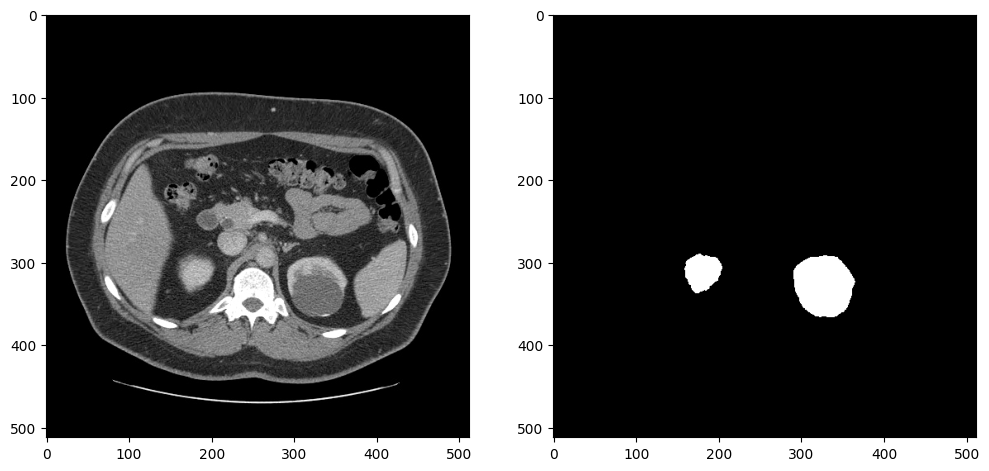

def __len__(self):

return len(self.dataset)データローダーが予期した出力を返すかテストするため、イメージとマスクを表示します。画像とマスクは、サイズ変更と前処理の後、データローダーによって返されます。このデータセットには腎臓のないスライスが多数含まれているため、少なくとも 5000 の腎臓ピクセルを含むスライスを選択して、アノテーションが正しく見えることを確認します:

dataset = KitsDataset(BASEDIR)

# 腎臓の注釈を含むスライスを検出

# item[0] はアノテーション: (id, annotation_data)

image_data, mask = next(item for item in dataset if np.count_nonzero(item[1]) > 5000)

# 余分な画像次元を削除し、視覚化のために画像を回転および反転

image = rotate_and_flip(image_data.squeeze())

# データローダーは、注釈を (インデックス、マスク) として返し、マスクを形状 (H、W) で返す

mask = rotate_and_flip(mask)

fig, ax = plt.subplots(1, 2, figsize=(12, 6))

ax[0].imshow(image, cmap="gray")

ax[1].imshow(mask, cmap="gray");Created dataset with 69 items. Base directory for data: kits19_frames_1